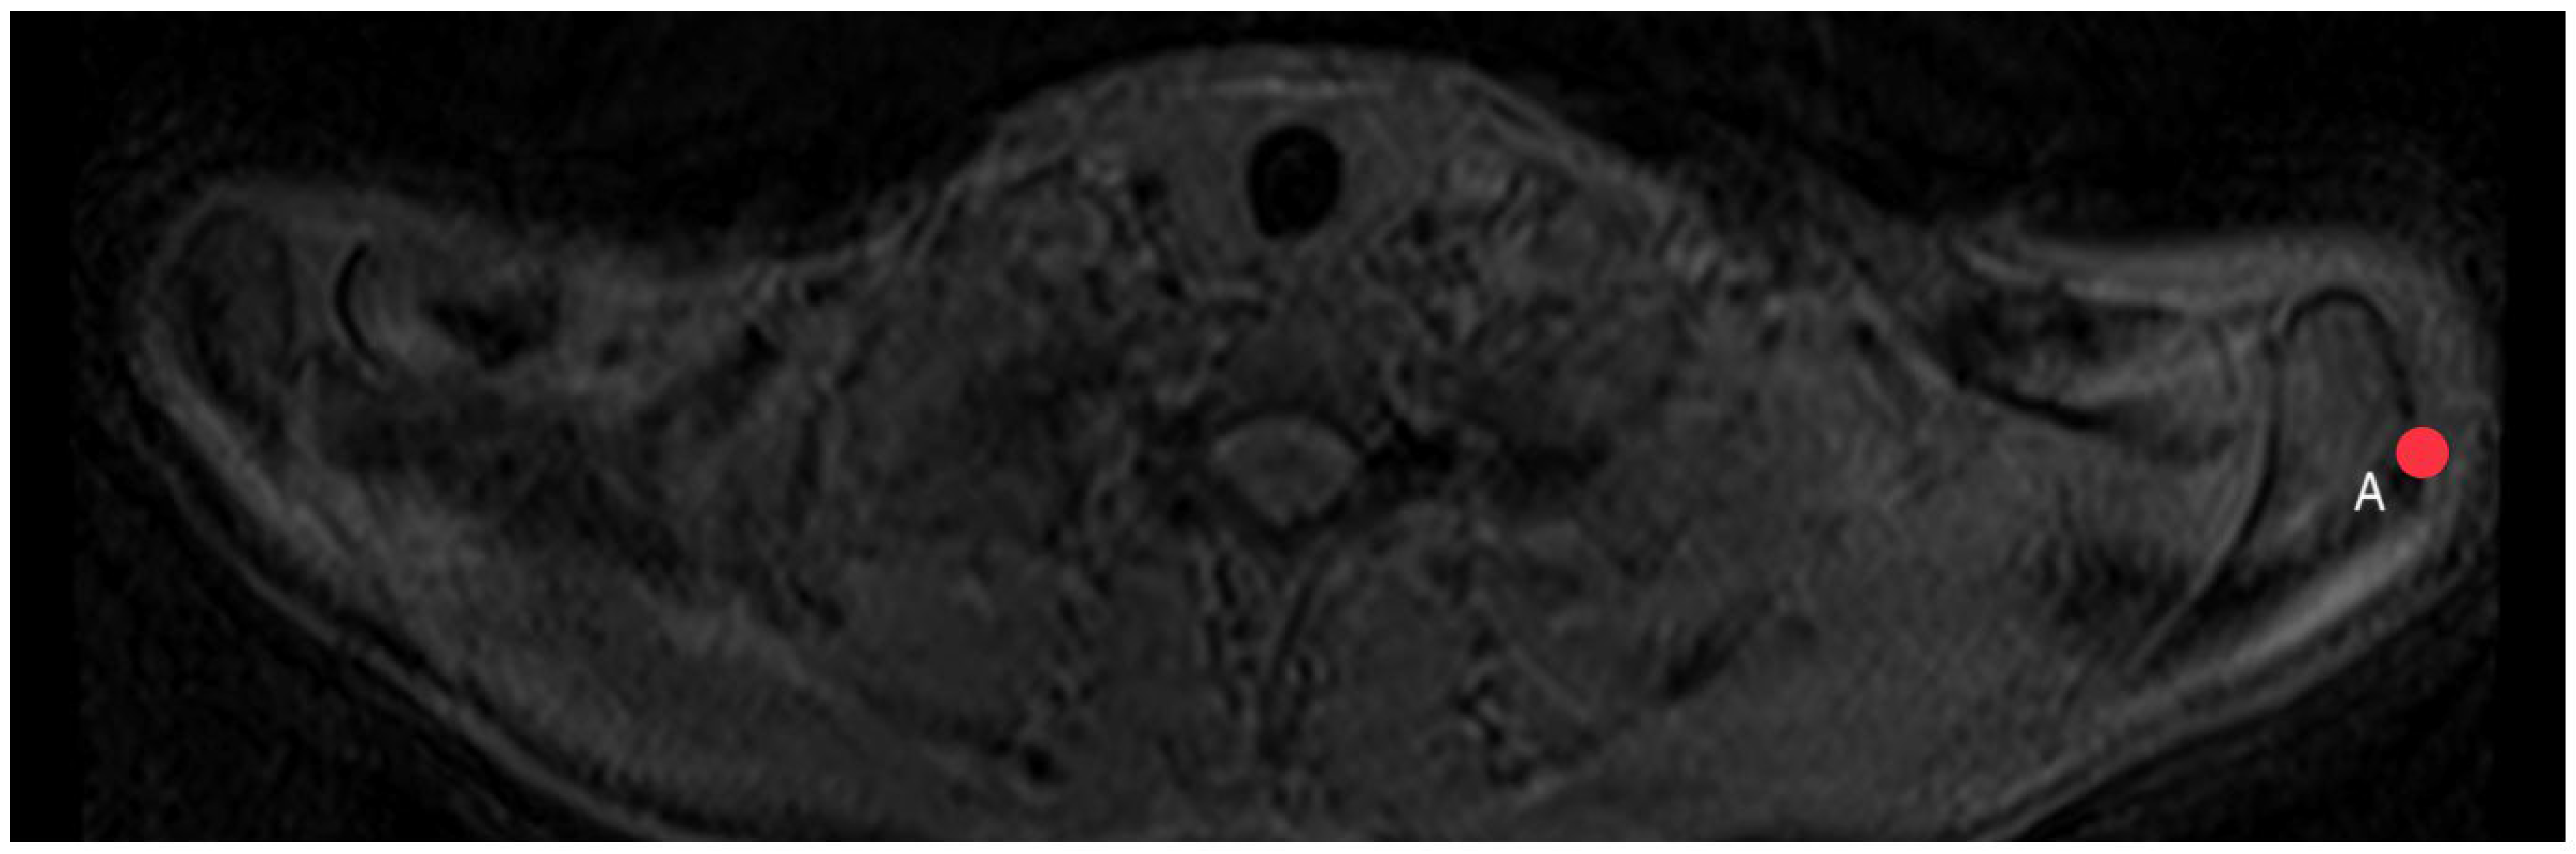

2.4. Acromion Tilt (Figure 6)